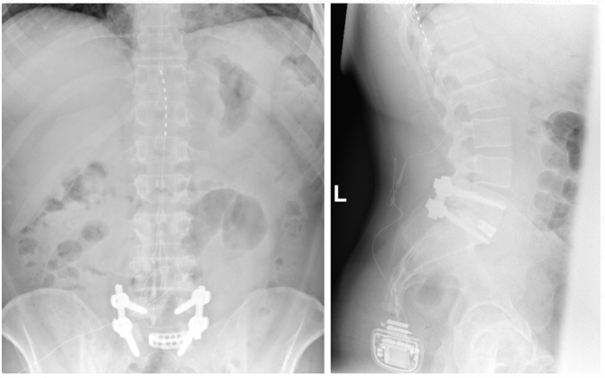

Bei der Rückenmarkstimulation wird in der Wirbelsäule eine Elektrode platziert. Über diese werden elektrische Impulse an das Rückenmark abgegeben. Die Elektrode ist mit einem Impulsgeber (vergleichbar mit einem Herzschrittmacher) verbunden. Das operative Verfahren gliedert sich in zwei Abschnitte: Im ersten Eingriff erfolgt, unter örtlicher Betäubung und Röntgenkontrolle, die Platzierung der Elektrode im Rückenmarkskanal. Im Anschluss erfolgt eine Testphase. Ziel ist es, die Abdeckung des Schmerzareals durch die Stimulation und die daraus resultierende Schmerzreduktion zu testen. Bei zufriedenstellendem Ergebnis wird in einem zweiten Eingriff der Impulsgeber unter die Haut implantiert.

Röntgenbild zur Rückenmarkstimulation